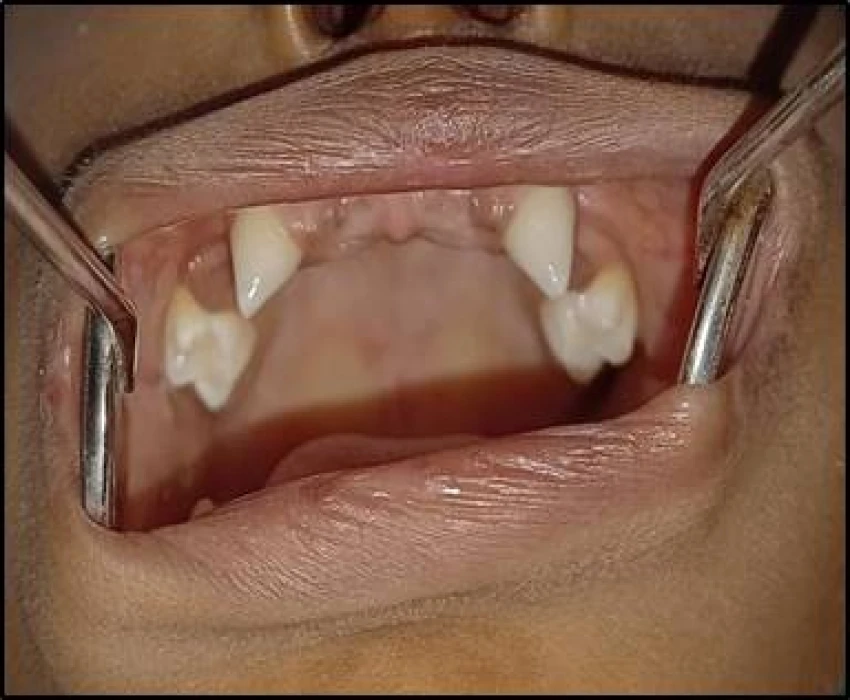

A 5 years old male patient reported to the Department of Oral Medicine and Radiology with a chief complaint of delayed eruption of teeth in lower front region of jaw since 2 years. Diagnosis of Hypohidrotic ectodermal dysplasia was given.

Hypohidrotic ectodermal dysplasia (HED) is characterized by hypotrichosis (sparseness of scalp and body hair), hypohidrosis (reduced ability to sweat), and hypodontia (congenital absence of teeth).The cardinal features of classic HED become obvious during childhood.Physical growth and psychomotor development are otherwise within normal limits.

Diagnosis is based on the episodes of hyperpyrexia, lack or type of the hair, absence of teeth and tooth buds and tooth morphology. Molecular testing approaches can include serial single-gene testing and a multigene panel.